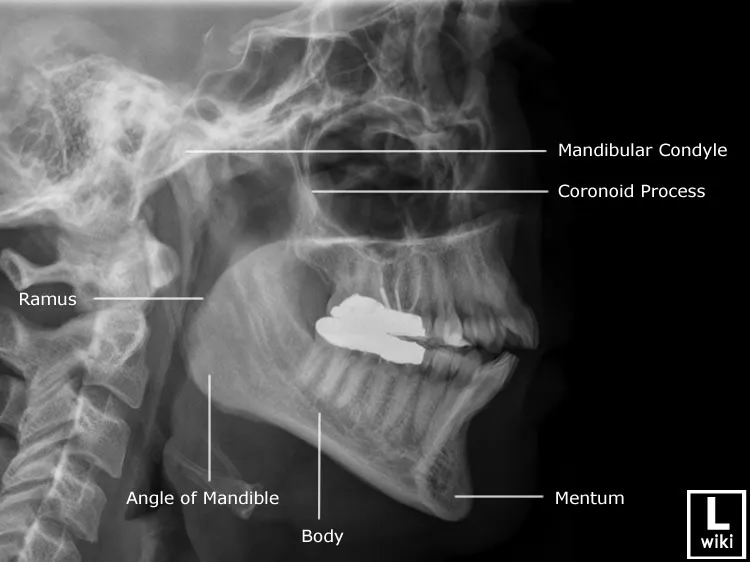

this isnt my xray but he will remove my 2 lower incisors and all wisdom teeth which will push my jaw back with my braces aswell in preparation then he will cut my jaw and move my whole jaw forward and ccw rotate it add a genioplasty if I still need it what do u think

yea my mandible is basically the same in that pic except my ramus is longer